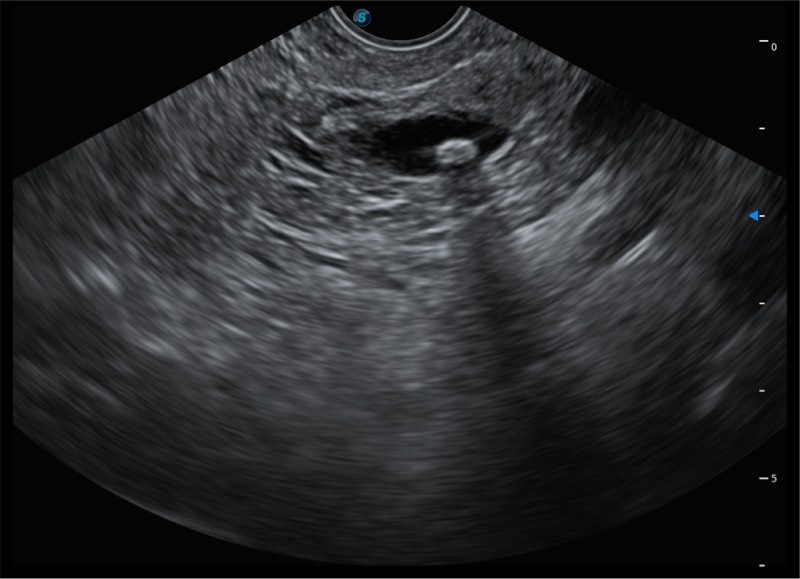

搭载百万级CMOS成像技术

及自主研发凸阵换能器,

可呈现优质的内镜和超声画面

基于二十年的超声技术积累,云顶集团官网提供了最新一代的独立超声主机,在提供高质量图像的同时满足多学科使用。具备常见多普勒技术并提供弹性成像、声学造影等高端影像技术。新一代传感器具有更强的抗干扰能力并减少图像伪影。